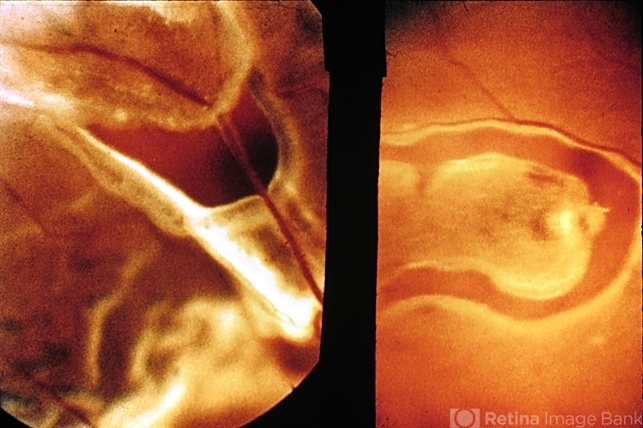

- retinal tear, retinal hole, vitreous hemorrhage

- Retinal tears at or near major retinal vessels. The vessel bridging the retinal hole (left) may be the source of vitreous hemorrhage. (Courtesy of E. D. Norton, M.D.)